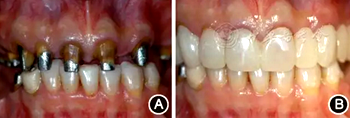

口腔衛(wèi)生狀況一般,菌斑指數(shù)0~2,鄰面少量軟垢;牙齦齦緣鮮紅、水腫、質(zhì)軟,出血指數(shù)2~3,余牙牙齦輕度水腫,出血指數(shù)0~2;全口探診深度2~3 mm,個(gè)別位點(diǎn)探診深度達(dá)4~5 mm,鄰面可探及附著喪失;未查及牙齒松動(dòng)及根分叉病變;烤瓷固定橋修復(fù),冠邊緣密合度欠佳,位于齦下1~2 mm;、唇側(cè)崩瓷,邊緣暴露;上前牙牙齦線不協(xié)調(diào);缺失,右下后牙可摘局部義齒修復(fù),固定橋修復(fù);近中面銀汞充填,近中懸突及繼發(fā)齲;上前牙覆蓋下前牙牙冠的1/2~2/3(圖1)。

圖1 患者初診時(shí)臨床照片 A:正面微笑像;B:正面口內(nèi)像